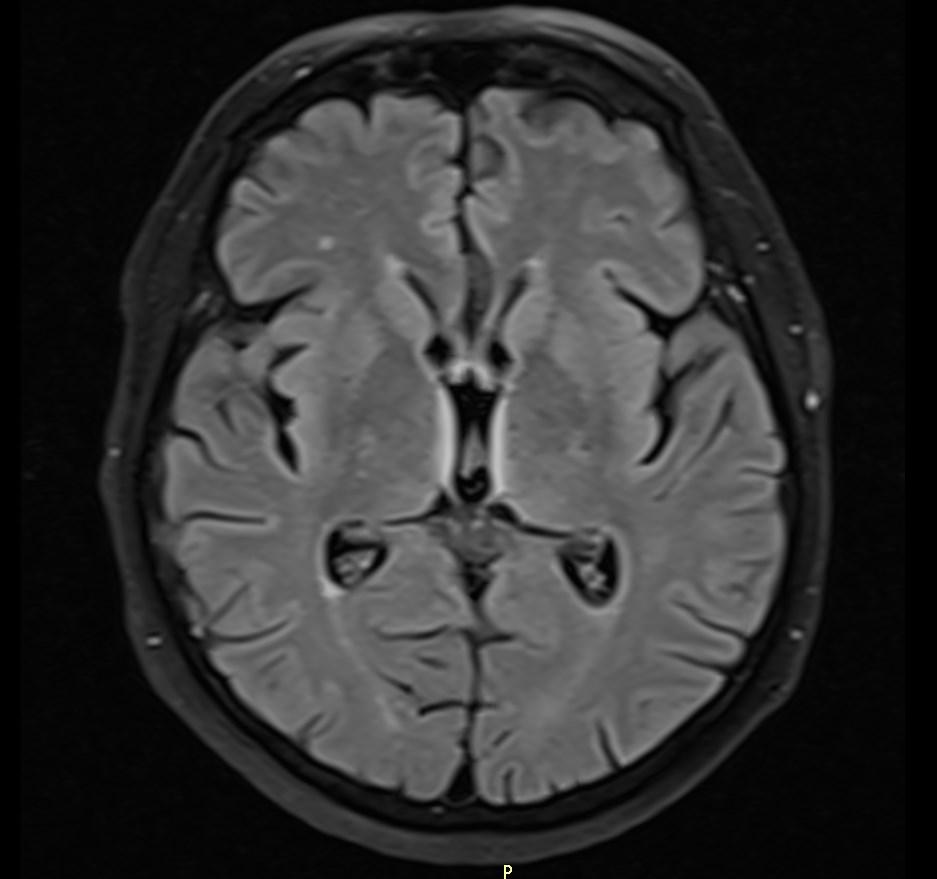

MRI images revealed hyperintensities in the periaqueductal region and the medial thalami.

T2/FLAIR: symmetrically increased signal intensity in the mamillary bodies, dorsomedial thalami, tectal plate, periaqueductal area, and around the third ventricle.